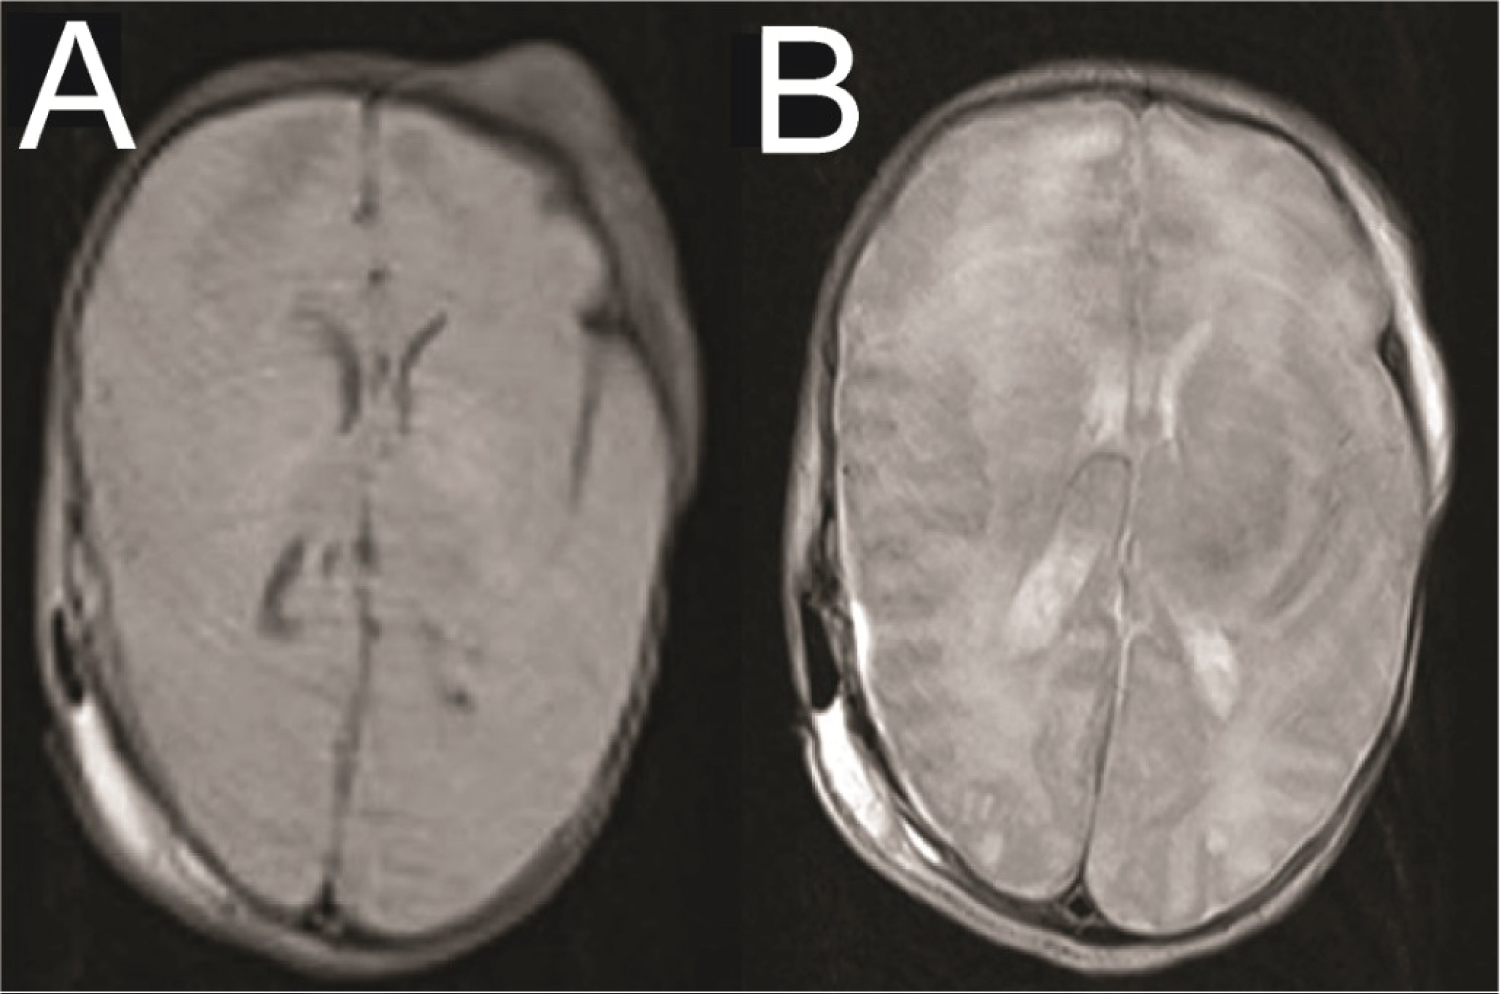

Neurology was consulted to facilitate continuous EEG monitoring. To better characterize the extent of the intracranial hemorrhage and limit radiation exposure, a Half-Fourier Acquisition Single-shot Turbo Spin Echo Magnetic Resonance Imaging (HASTE MRI) of the brain was performed. The results showed an expanded EDH, a 5 mm midline shift, and a trapped right ventricle (Figure 3). A repeat hematocrit returned at 32%.

Figure 3: Pre-operative MRI brain HASTE protocol presented in T1 STIR. (A) Right parietal epidural hematoma, slightly increased in size from previous, with resultant mass effect on the right temporal and parietal lobes; (B) Trapped right ventricle with 5 mm midline shift; (B, C) Reduced diffusion along the bilateral temporal and parietal lobes with signal characteristics suggestive of subarachnoid hemorrhage. View Figure 3

The night following the operation, the infant had another seizure. It was uncertain if these seizures were transient and due to the recent surgical intervention or if they were a sign of permanent neurologic damage. However, on postoperative day 1, no further seizure activity was detected, and the neurology team felt it was safe to discontinue EEG monitoring. A follow-up HASTE MRI (Figure 4) confirmed successful hematoma evacuation, absence of residual clots, and improved midline shift. She continued to do well and was advanced to oral feeding. The surgical incision demonstrated satisfactory healing.

Figure 4: Post-operative MRI brain HASTE protocol. (A, B) Axial views demonstrating adequate evacuation of the hematoma and improved midline shift. View Figure 4